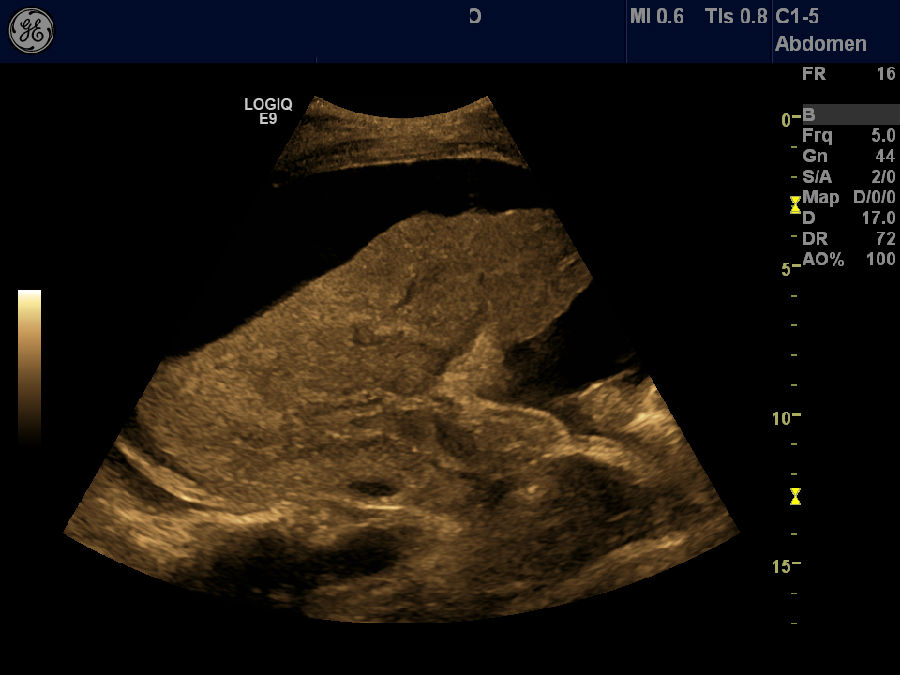

肝血管瘤

剑突下纵切,肝内高回声结节,血管瘤